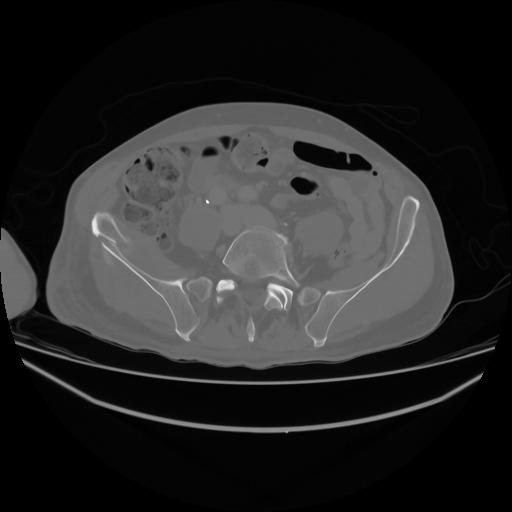

4 CUERPO,CE,Axial,3.0,CUERPO,,